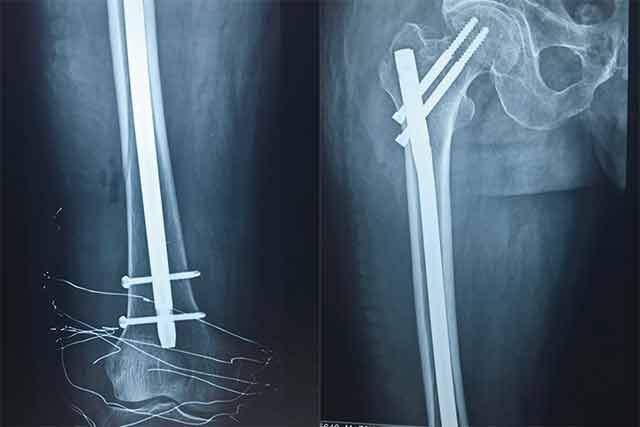

▲術(shù)后

經(jīng)過骨科專家團(tuán)隊(duì)的詳細(xì)查體以及相關(guān)拍片、CT等輔助檢查,韓大爺被診斷為右側(cè)的股骨干骨折合并同側(cè)粗隆間骨折。通過和病人及家屬耐心細(xì)致地溝通,韓大爺收住我院骨科。經(jīng)過詢問病史,了解到韓大爺有胃出血及疝修補(bǔ)手術(shù)史約10余年,并伴有老年高血壓病史,年事已高、病情復(fù)雜,需要制定更為詳細(xì)的診療方案。骨科主任楊連海及副主任孫守全立即組織科內(nèi)討論,充分與患者家屬進(jìn)行溝通、以得到家屬的認(rèn)可,細(xì)致而縝密地結(jié)合病人的個(gè)體情況定制手術(shù)方案。由于病情復(fù)雜,麻醉科主任修冬云在手術(shù)前親自看望韓大爺?shù)纳眢w狀況,認(rèn)真分析評(píng)估手術(shù)的風(fēng)險(xiǎn)程度,排除手術(shù)禁忌,選擇合適的麻醉方式。經(jīng)過積極的術(shù)前準(zhǔn)備,孫守全副主任擇期在硬膜外麻醉下完成了髖部骨折+同側(cè)股骨干骨折髓內(nèi)重建釘?shù)膬?nèi)固定手術(shù),手術(shù)過程非常順利,骨折復(fù)位基本達(dá)到解剖復(fù)位。術(shù)后經(jīng)過預(yù)防感染、鎮(zhèn)痛、預(yù)防下肢深靜脈血栓等治療,韓大爺恢復(fù)的非常好,沒有出現(xiàn)感染、血栓等并發(fā)癥,而且傷口甲級(jí)愈合。